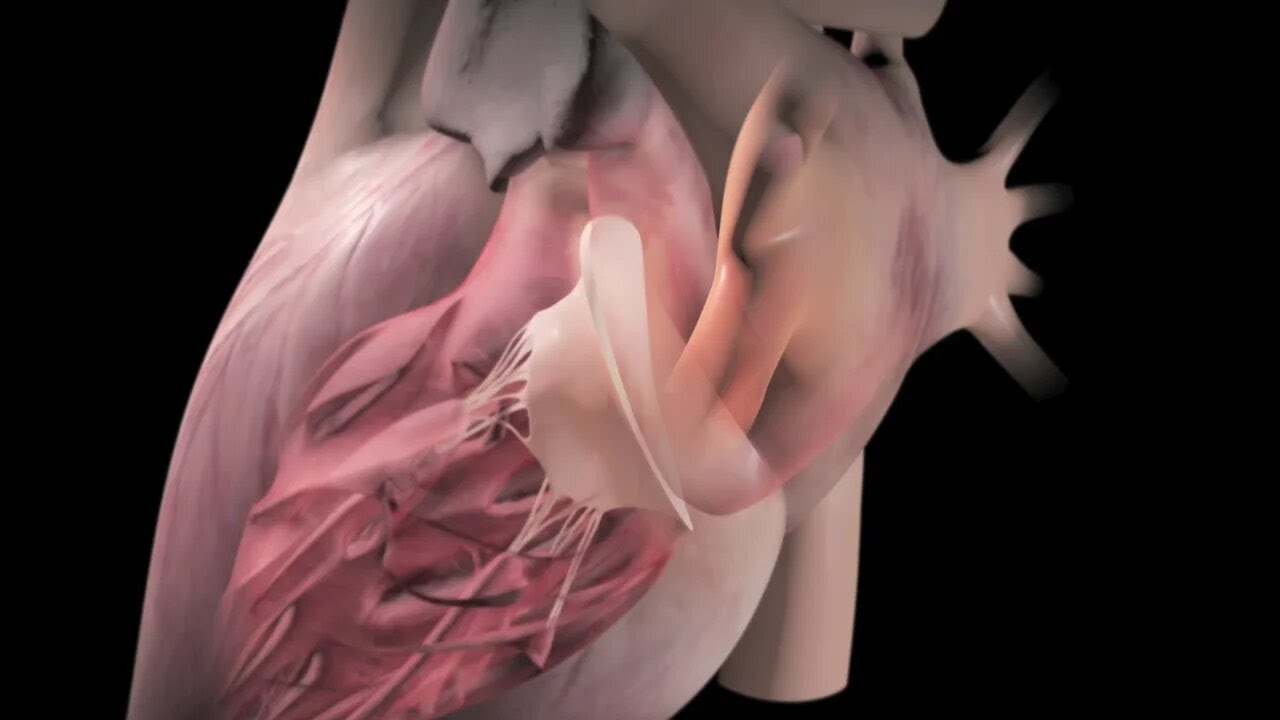

-Kalbin aort kapağının ameliyatsız yöntemle değiştirilmesi (TAVI)

-Kalbin mitral kapağındaki kaçağın mandal ile ameliyatsız tedavisi (MitraClip)

-Kalbin mitral kapağındaki darlığın balon ile ameliyatsız açılması (Mitral balon)